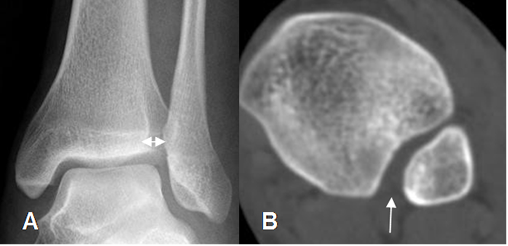

Fig 59 C. Lesión ligamentaria.

Rx AP. Leve aumento del espacio articular medial.

Fig 59 D. Lesión ligamentaria.

A: Rx lateral. Igual paciente anterior. No se encuentran alteraciones.

B: Rx lateral con stress. Aumento del espacio articular, con desplazamiento posterior de la tibia, por lesión ligamentaria.